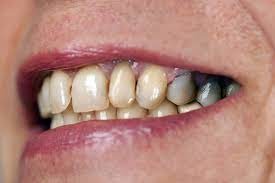

What Causes The Dark Line On My Gums?

You have seen smiles that you know have dental crowns in the front. You look at them and say to yourself that something is not natural. Many times, it is the dark rim of gum tissue that gives it away. The dark rim of gum tissue does not occur around natural teeth, only around teeth that have been covered with dental crowns.

The dark line is associated with an old porcelain dental crown. This style of dental crown is referred to as a porcelain fused-to-metal dental crown because it uses tooth-colored porcelain on the outside and it uses metal under the porcelain for strength. The dark line originates from the edge of the dental crowns where the porcelain and the metal meet at a knife-edge at the gum line. At the knife-edge, a very thin amount of the metal always shows. One of the illusionary techniques cosmetic dentists have used was to hide the thin dark line under the gum line. Over time, the gum tissue would recede and expose the dark line. In some patients the dark line would show through the gum and make it appear dark as well.

How Do You Get Rid of It?

The only way to eliminate the esthetic problem is to replace the dental crowns. When replacing just one single dental crown in the front, you should expect that it might take more than one try-in of the new dental crown before it is permanently cemented into place. Because your central incisors are the most prominent teeth in the mouth, matching them is the most difficult esthetic challenge. Only the best dental technicians are able to mimic one central incisor tooth next to another.

What Are Some of the Replacement Dental Crowns Like?

Some of the clever ways dentists and dental technicians have been able to mimic natural teeth is through the new advancements in dental materials. New all-tooth-colored ceramic dental crowns are the latest technological advancement cosmetic dentists have to recreate natural teeth. In comparison to porcelain fused-to-metal dental crowns, all-ceramic dental crowns do not contain any metal, thus no dark line can appear.